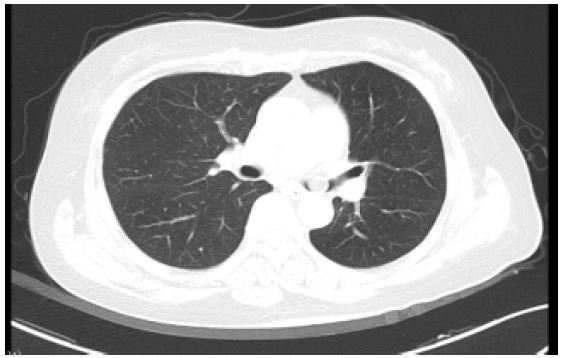

Physical and laboratory examination: On her physical examination, she had minor shortness of breath and inspiratory phase wheezing rales were heard in left upper lung. Laboratory workup was remarkable for leukocytosis (11.1 cells × 109/l). Nothing abnormal detected in tumor markers including SCC antigen, neuron specific enolase, carbohydrate antigen (CA125, CA199, CA153). Both anti-neutrophil cytoplasmic antibody (P-ANCA MPO, PR3) and anti-glomerular basement membrane antibody GBM were negative. An enhanced computed tomography (CT) scan demonstrated a nodule with CT value of-100HU in left main trachea, and inflammation in left lower lobe (Figure 1).

Figure 1: Chest Enhanced Scan showed Airway nodule in left main trachea (CT value - 100 HU).